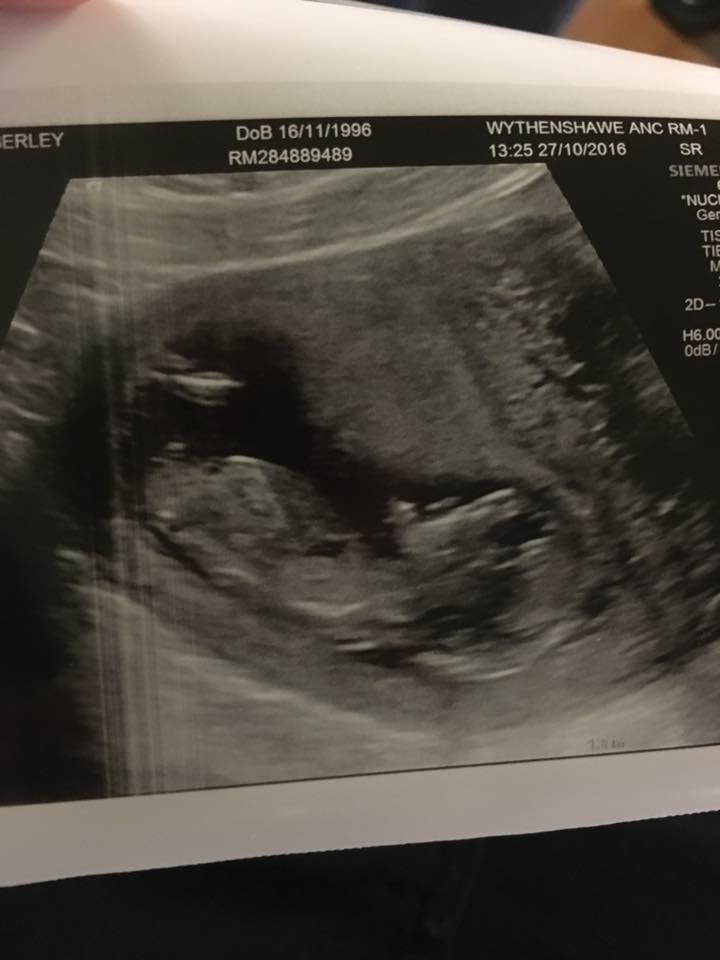

Just like any other parent to be I'm to impatient to wait for my 20wek scan to find out what I'm having , I have heard about the skull theory but I'm having a hard time deciding still wether it's a girl or boy so could anyone help me Attachment 33554